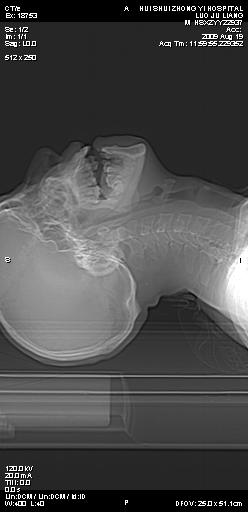

标题: CT21693:男 58岁 右侧咽部疼她2天余 PE:右侧扁桃体肿大 压痛 [打印本页]

标题: CT21693:男 58岁 右侧咽部疼她2天余 PE:右侧扁桃体肿大 压痛

喉部新生物,喉癌可能大,建议喉镜取组织活检。

右化脓性扁桃体炎症伴咽后壁脓肿形成.